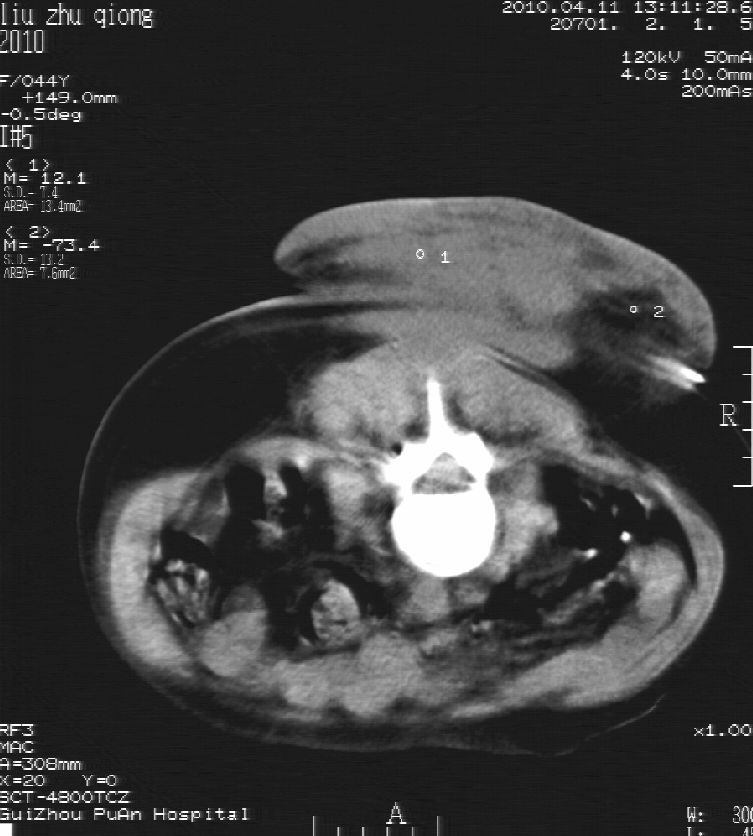

刘某,女,44岁,生第一胎时发现腰背部肿块,黄豆大小,至今17年,呈逐年增大,现行ct检查如下,敬请各位指点。

病史:女,44岁,腰背部肿块,黄豆大小,17年,呈逐年增大。

ct示:骶骨见软组织密度影,似见细条状,或花边状高密度影,考虑不典型钙化灶,向后生长,超出皮肤,可见骶骨破坏,第5幅ct图似与骶管相通。

诊断:脊索瘤

病程长,生长慢,肿块巨大,考虑神经纤维瘤,脂肪密度可以用肿瘤生长过程中包裹入皮下脂肪解释。